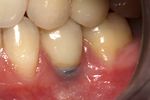

Fixture show

Recession of the gingiva leads to exposure of the metal abutment under a dental crown.

Black triangles

Black triangles caused by bone loss between implants and natural teeth